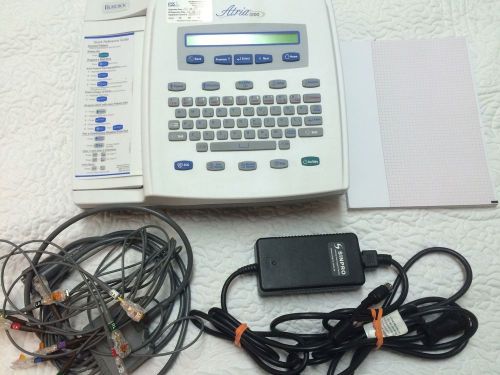

Burdick Atria 3100 Ekg Machine